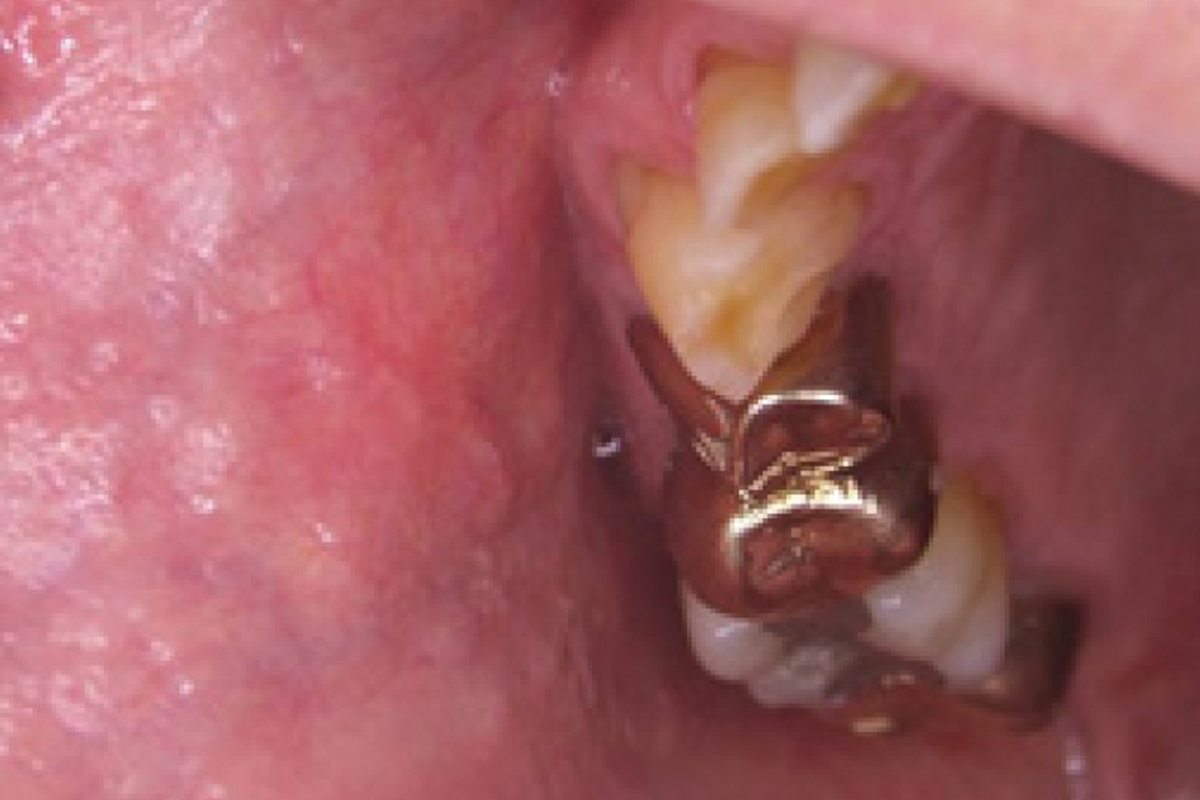

TRAITEMENT HÉMANGIOME DANS LA CAVITÉ ORALE